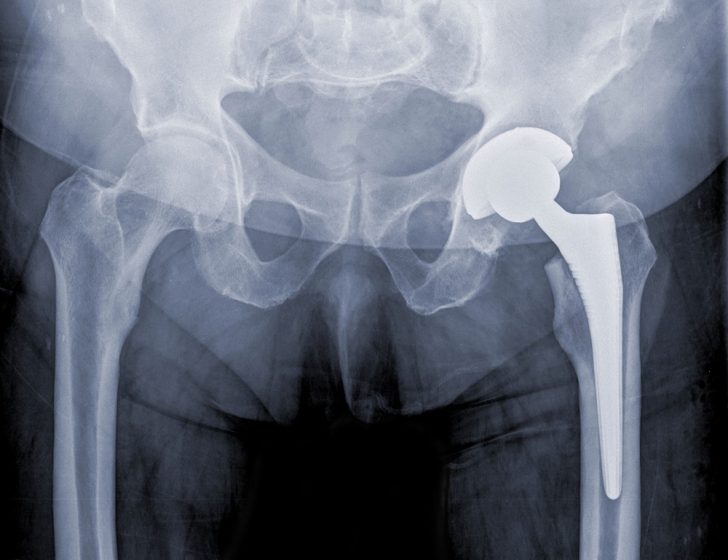

traditional, successful hip replacement

Hip Replacement

A newer type of artificial hip could be a good option for patients who need their original replacement taken out, according to a new study.

Although hip replacement surgery is great at relieving pain and restoring mobility, dislocation is a common complication of the procedure. The risk of this is highest in patients who have had a second hip replacement, and that procedure is known as “revision surgery.”

Now, though, research conducted by Dr. Geoffrey Westrich and colleagues at Hospital for Special Surgery, in New York City, and other joint replacement centers indicates that a newer type of artificial hip known as a “modular dual mobility” implant could be a good choice for patients who need a revision surgery.